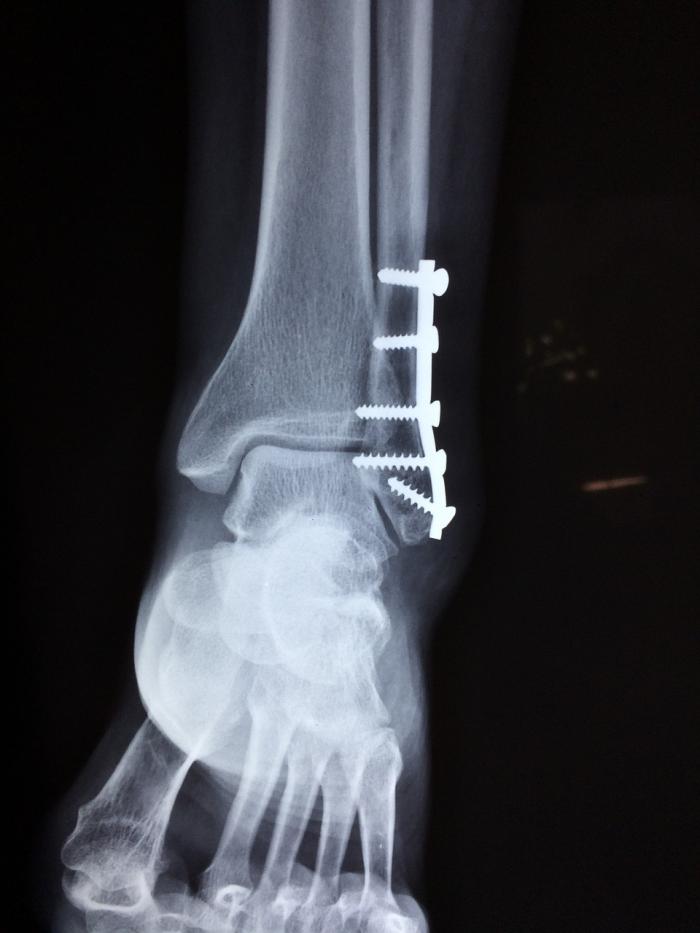

O fractura de glezna poate varia de la o simpla fisura osoasa fractura fara deplasare care poate sa nu va impiedica sa mergeti pe piciorul fracturat pana la fracturi complexe severe care fac imposibil. In mod obisnuit medicii imobilizeaza glezna intr o atela gipsata timp de maxim 2 saptamani sau pana cand se reduce edemul perimaleolar. Fractura bimaleolara glezna dr cu subluxatie externa a piciorului dr in urma cu o luna am suferit o fractura bimaleolara glezna dr cu subluxatie externa a piciorului dr motiv pentru care am fost operat punandu mi se o tija fixata cu opt suruburi la nivelul peroneului.